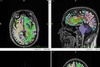

암 치료에서 운동의 위상이 빠르게 달라지고 있다. 체력 관리나 재활 차원의 '보조 요법' 정도로만 여겨졌던 운동이 이제는 암세포의 성장과 전이를 직접 억제하는 과학적 치료 전략, 이른바 '4번째 항암제'로 자리매김하고 있다는 평가가 잇따르고 있다. 반면 오랫동안 누구에게나 권고돼 온 '보편적 건강식'은 정밀의학의 시대를 맞아 사실상 종말을 향하고 있다. 암 예방과 치료의 관점에서 볼 때 이제는 모든 사람에게 똑같이 좋은 음식은 없다는 인식이 학계의 공통된 결론으로 자리 잡고 있기 때문이다. 이달 초 전남 여수에서 열린 '나파'(NAPA·Nutrition and Physical Activity on Aging, Obesity and Cancer) 국제학술대회에서는 한국과 미국, 일본, 유럽 등지의 장수·암 연구 석학 300여명이 모여 운동과 영양을 둘러싼 이러한 패러다임 전환을 집중 조명했다. 나파 송용상 회장(서울의대 산부인과 명예교수, 명지병원 부인암센터장)은 "암과 만성질환의 치료 패러다임이 분명히 바뀌었다"며 "이제는 병원에서의 치료를 넘어, 무엇을 먹고 어떻게 움직이느냐를 분자 수준에서 분석하는 '정밀 생활 의학'이 필수가 됐다"고 선언했다. ◇ 운동